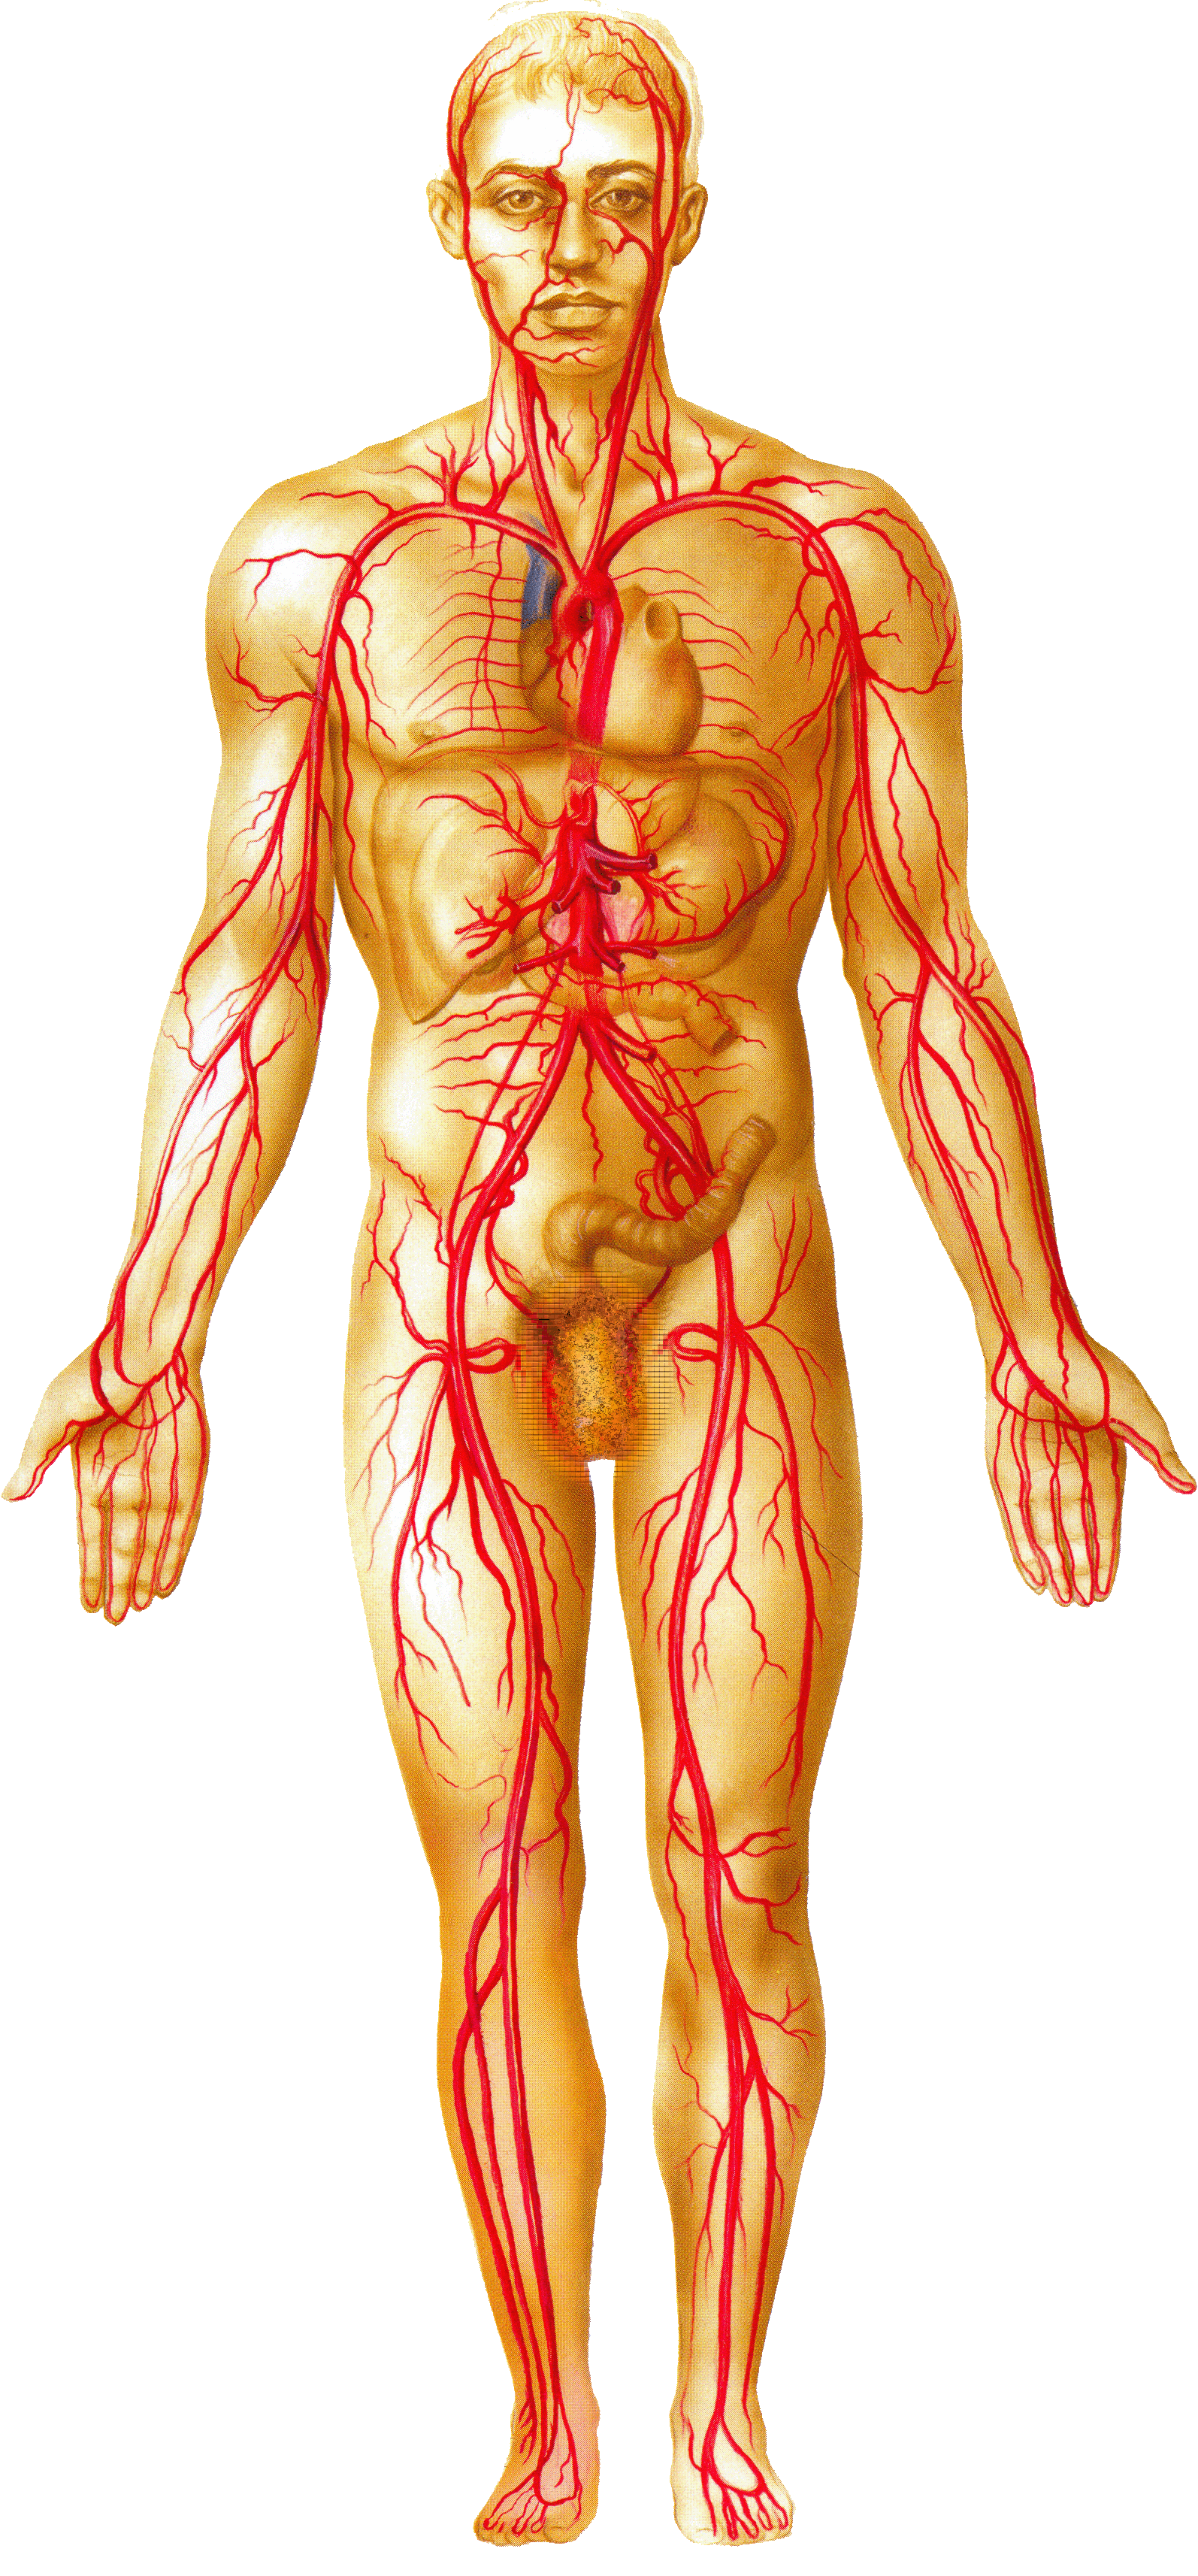

Анатомия человека: кровеносная система и её связь со скелетом